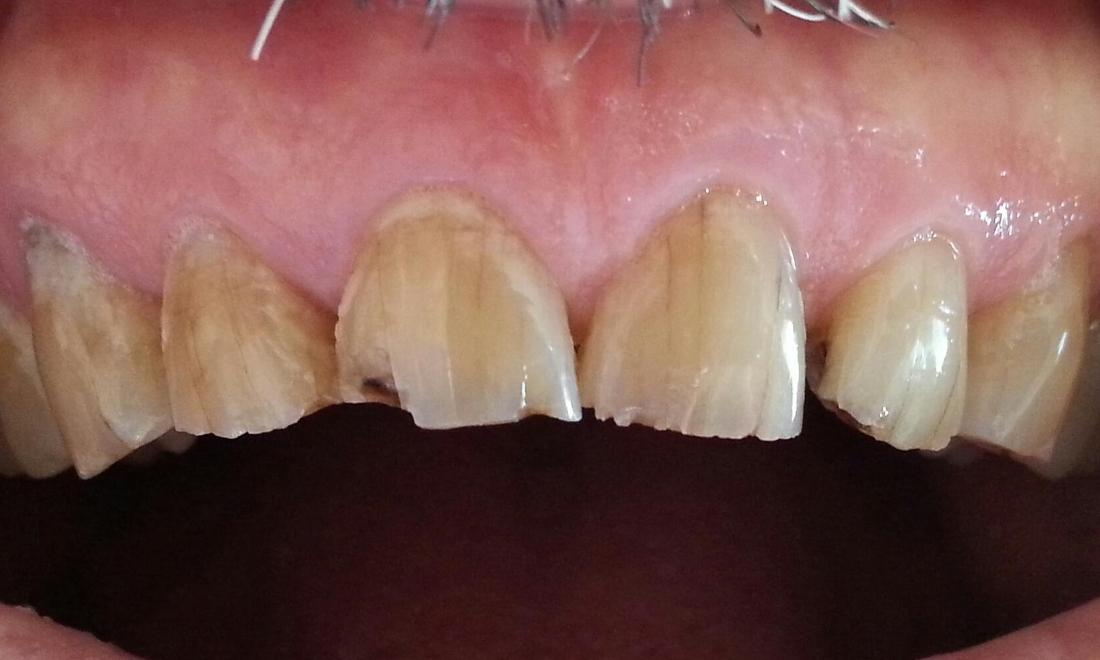

Lots of wear and tear had weakened this patients teeth over time and he was becoming concerned about their appearance. By using strong, cosmetic porcelain crowns, Dr. Lutwin was able to address this patient’s wishes to both make his teeth stronger and his smile more attractive. Now, every time we see this wonderful patient he says: “I should have done this a long time ago!”